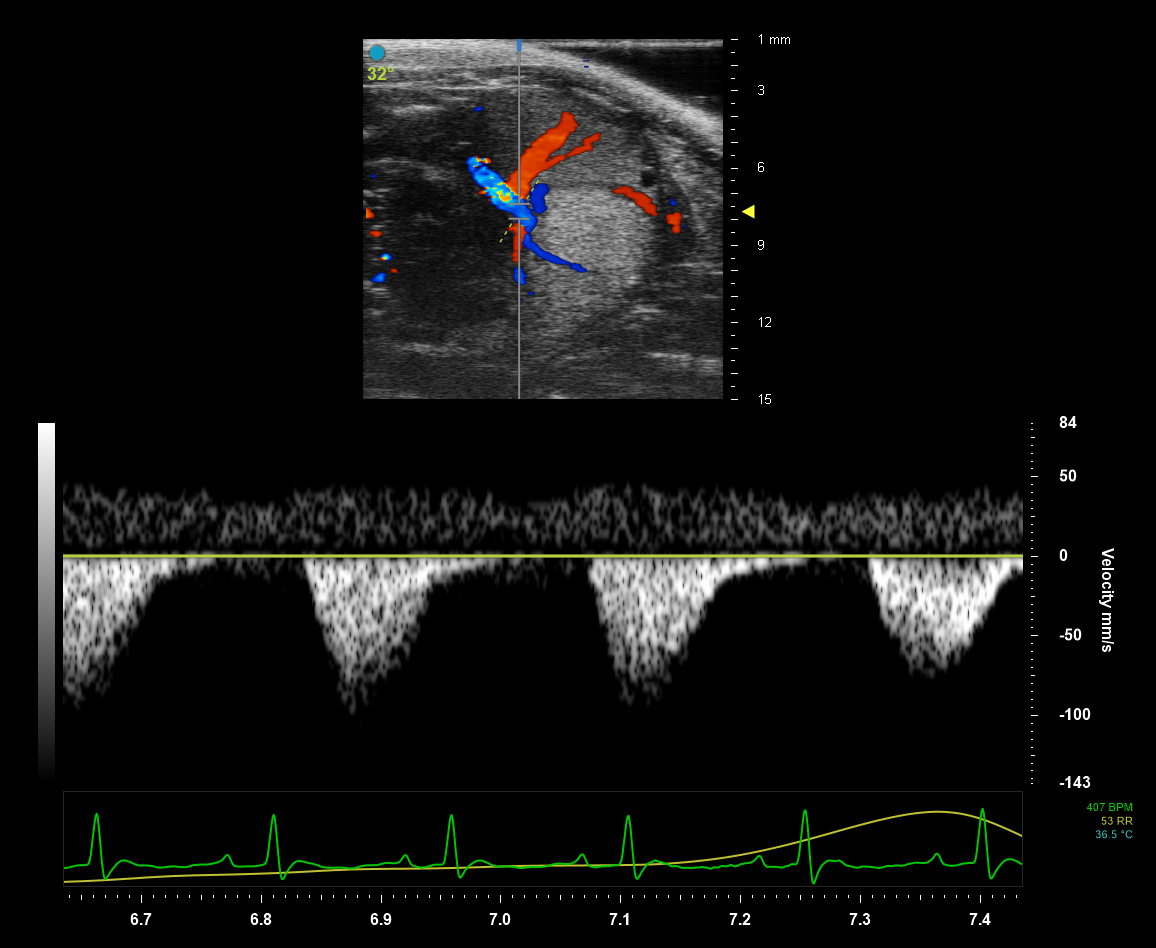

High Frequency Ultrasound and Photoacoustic Imaging

Our High Frequency Ultrasound transducers deliver an acoustic pulse into the small animal’s body. Tissues of different densities absorb and reflect sound waves differently resulting in highresolution grayscale images when the partially reflected sound waves return to the transducer. Photoacoustic imaging allows the delivery of light energy that is absorbed by tissues causing a thermoelastic expansion. This expansion then generates ultrasound waves that are detected by the transducer and produce images of optical absorption contrast within tissues. New laser technology provides faster, more sensitive image acquisition at a wider wavelength range (680 - 970 nm and 1200 - 2000 nm).